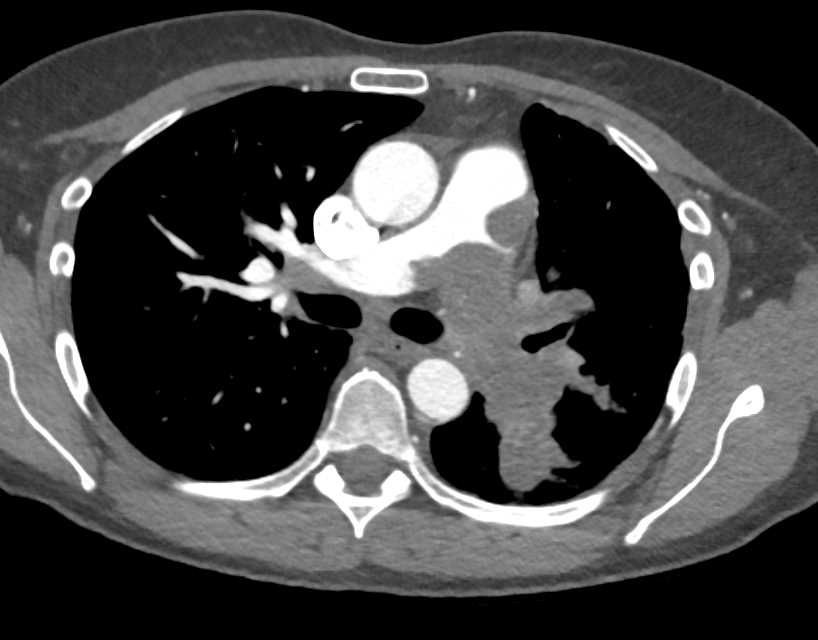

Pulmonary Artery Sarcoma